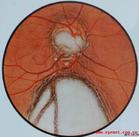

常單眼發病。為胚胎時眼泡胚胎閉合不全所致,常伴有脈絡膜缺損,而僅有視盤缺損則少見。患者視力明顯減退,視野檢查生理盲點可能。

視盤大,可為正常的數倍。缺損區為淡青色,邊緣清,凹陷大而深,多位於鼻側,血管僅在缺損邊緣處穿出,呈鉤狀彎曲。可伴有虹膜脈絡膜去孫及其他先天性眼部異常。

患者視力明顯減退,視野檢查生理盲點可能。視盤大,可為正常的數倍。缺損區為淡青色,邊緣清,凹陷大而深,多位於鼻側,血管僅在缺損邊緣處穿出,呈鉤狀彎曲。可伴有虹膜脈絡膜去孫及其他先天性眼部異常。

為胚胎時眼泡胚胎閉合不全所致,常伴有脈絡膜缺損,而僅有視盤缺損則少見。